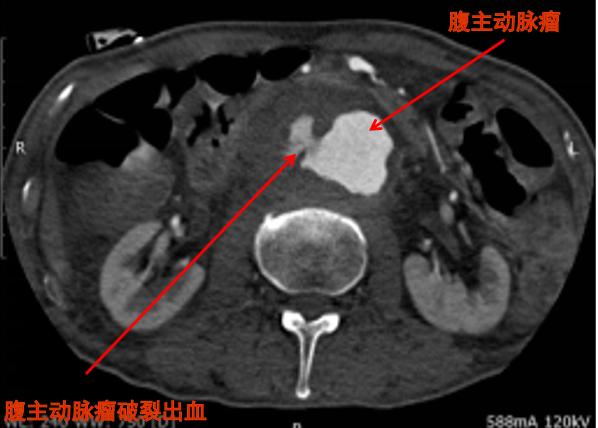

因为CT扫描速度很快,密度分辨力强,无论是对于胃肠道穿孔、出血、扭转、梗阻,胆道或是尿路的结石,肝、脾或肾脏的破裂,肠系膜血管的血栓性闭塞,腹主动脉瘤破裂或夹层,阑尾或憩室的炎症,还是腹腔或腹膜后的肿瘤等,都能够得到比较清晰的细节显示,诊断价值都比较高。

CT清楚显示腹主动脉瘤并破裂出血,病情凶险